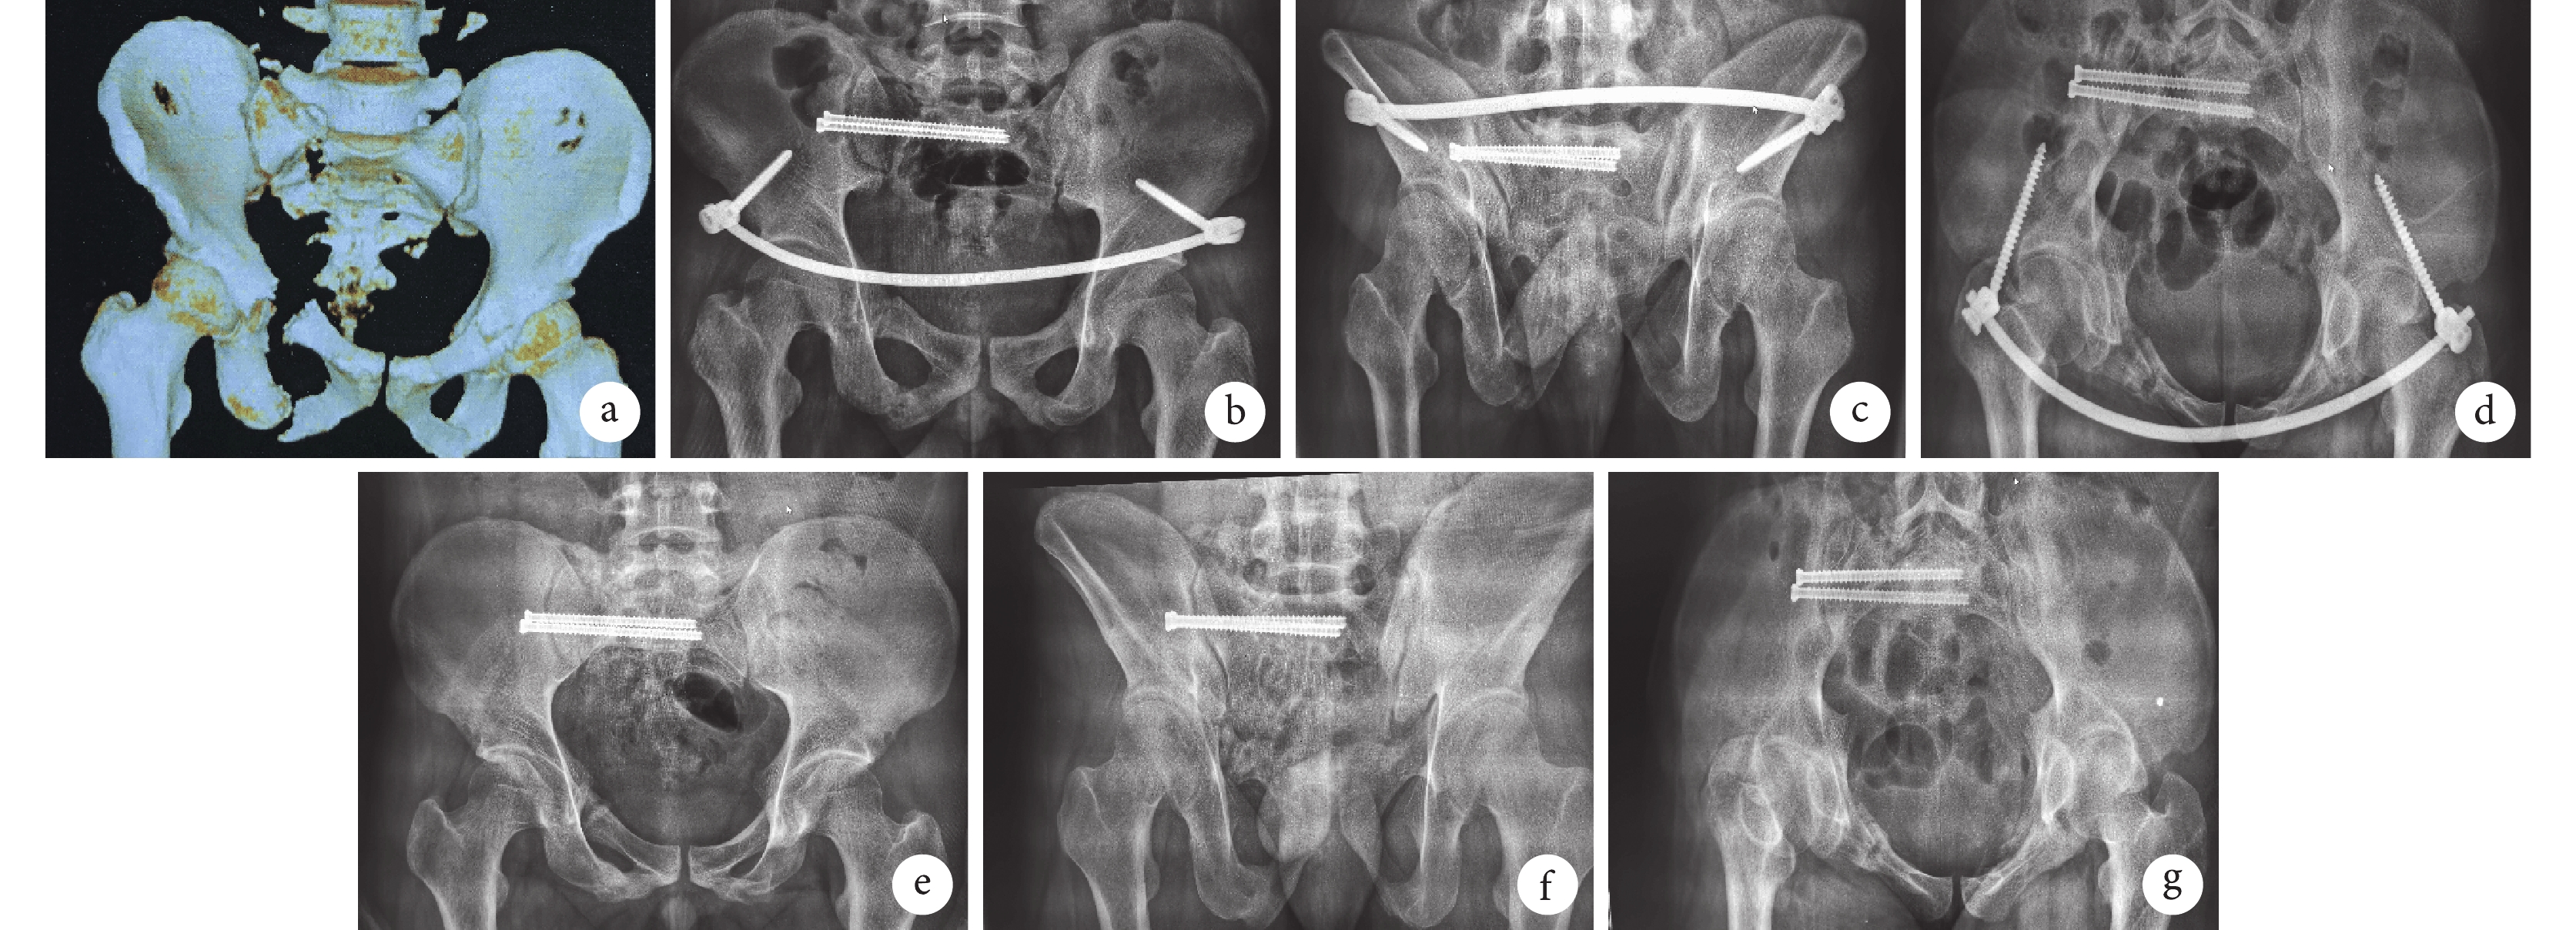

對照組患者,男,23歲,交通事故傷致Tile C1.3型骨盆骨折

a. 術前骨盆CT三維重建;b~d. 術后1個月骨盆前后位、出口位、入口位X線片;e~g. 術后1年骨盆前后位、出口位、入口位X線片

Figure1. A 23-year-old male patient with Tile C1.3 pelvic fracture caused by traffic accident in the control groupa. Three-dimensional CT reconstruction of pelvis before operation; b-d. Pelvic X-ray films of anteroposterior, outlet, and inlet views at 1 month after operation; e-g. Pelvic X-ray films of anteroposterior, outlet, and inlet views at 1 year after operation